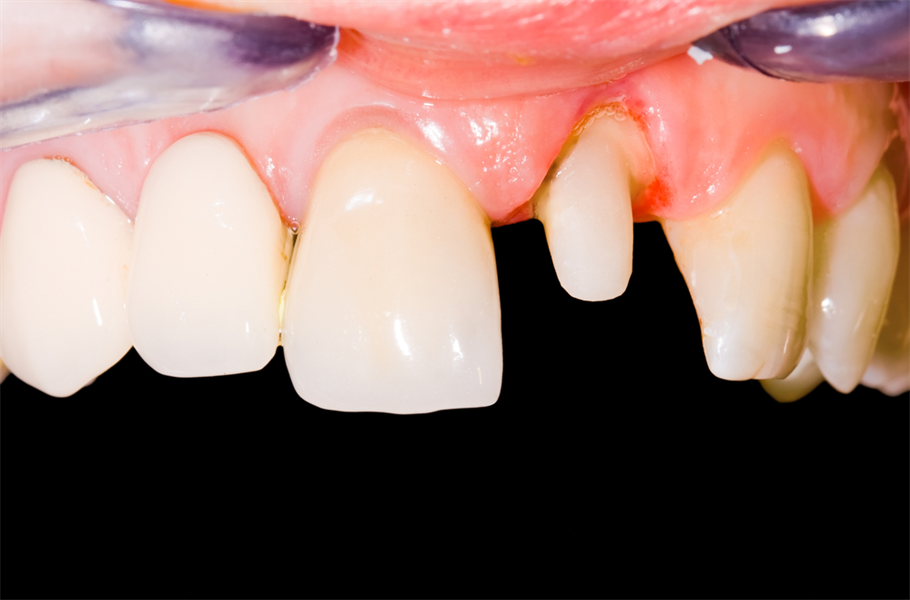

When To Save A Tooth? Part 2: To Save or Not to Save

In today’s article, we continue to discuss the pros and cons of saving a tooth versus replacing it with an implant-supported crown. Deep decay or fracture of natural teeth generally requires root canal therapy. This is an added expense that should be weighed against the cost of the extraction and...  Read More